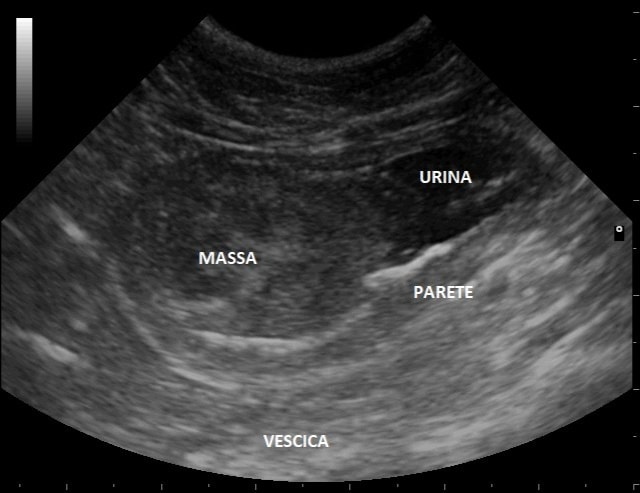

Le urine possono essere raccolte dal proprietario nel momento in cui l’animale le produce, ed è una modalità di raccolta indicata per esami di controllo. Se invece il veterinario richiede l’analisi batteriologica e l’antibiogramma, la modalità di prelievo migliore è la cistocentesi ecoguidata, ovvero con l’aiuto dell’ecografia visualizziamo la vescica e preleviamo l’urina con una siringa, in modo asettico.

No, l’esame delle urine è utile per avere un quadro generale del benessere delle vie urinarie e dell’organismo, ma se riscontriamo delle alterazioni, queste vanno approfondite con esami collaterali. Ad esempio, di fronte a un cane che beve e urina molto, potremmo trovarci un peso specifico basso. A questo punto ci chiediamo: il cane ha un problema renale o un problema ormonale? Dobbiamo associare gli esami del sangue ematochimici completi. Se i parametri renali sono nella norma, allora indagheremo un possibile iperadrenocorticismo o un diabete insipido (ve ne parleremo nei prossimi articoli). Al contrario, se i parametri renali sono molto alterati, la diagnosi sarà d’insufficienza renale. Portiamo un altro esempio: gatto anziano che fa le urine col sangue. Il proprietario ci porta le urine ed effettivamente sono rosse. E’ sufficiente per diagnosticare una cistite? No, meglio eseguire un’ecografia addominale perché potremmo riscontrare un tumore in vescica che sta sanguinando.